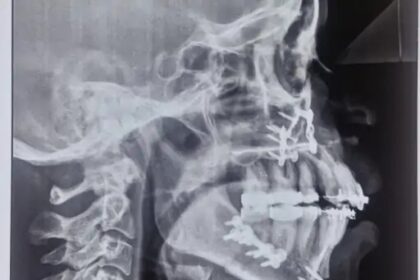

सिम्स में युवती के बाहर निकले दांतों की सर्जरी लाखों का इलाज आयुष्मान कार्ड से मुफ्त में हुआ

बिलासपुर ,01 फरवरी(वेदांत समाचार)। बिलासपुर के सिम्स अस्पताल के दंत चिकित्सा विभाग…